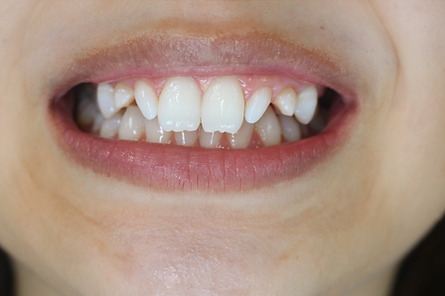

1矯正・マウスピース【治療例2】

治療前